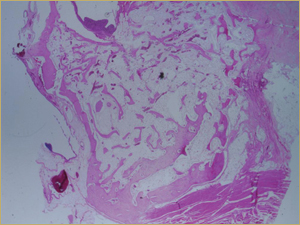

Figure 5a: Low-power histologic examination of rabbit maxillary sinus augmented with low-dose (10 mg) bone morphogenetic protein at 2 weeks after procedure. H&E stain, 50× magnification.

There was no difference in appearance between sinuses augmented with low-dose (10 mg) BMP bioimplants (Fig. 5a) and those augmented with high-dose (25 mg) BMP bioimplants (Fig. 5b). Both groups had a high concentration of thin, woven bony trabeculae, which were smaller and more numerous than in sinuses with either autografts or DBM bioimplants.